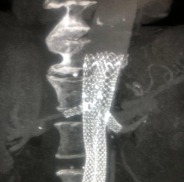

Ultra-Low Profile FEVAR-Implantat

Optionen für eine doppelte oder einfache Fenestrierung sind erhältlich, mit oder ohne Ausschnitt (Scallop) an der oberen Eingeweidearterie. Fenestrierte Iliakal-Komponenten sind ebenfalls erhältlich.

Das Meridian™ Endograft-System ist ein nicht standardisiertes Implantat für die individuelle Behandlung von Patienten. Es ist nicht CE-gekennzeichnet und wird nur für individuelle Patienten geliefert.